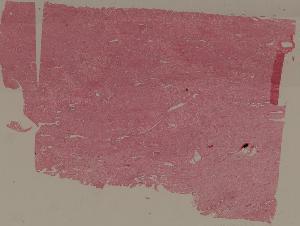

88. Chronic cavitary tuberculosis of the lung

89. Tuberculous lymphadenitis

90. Lepromatous leprosy of the skin

91. Tuberculoid leprosy

92. Typhoid fever of intestine

95. Poliomyelitis

96. Pulmonary aspergillosis

97. Amebic colitis

98. Schistosomiasis of the colon

99. Experimental acute schistosomiasis of the liver (rabbit)